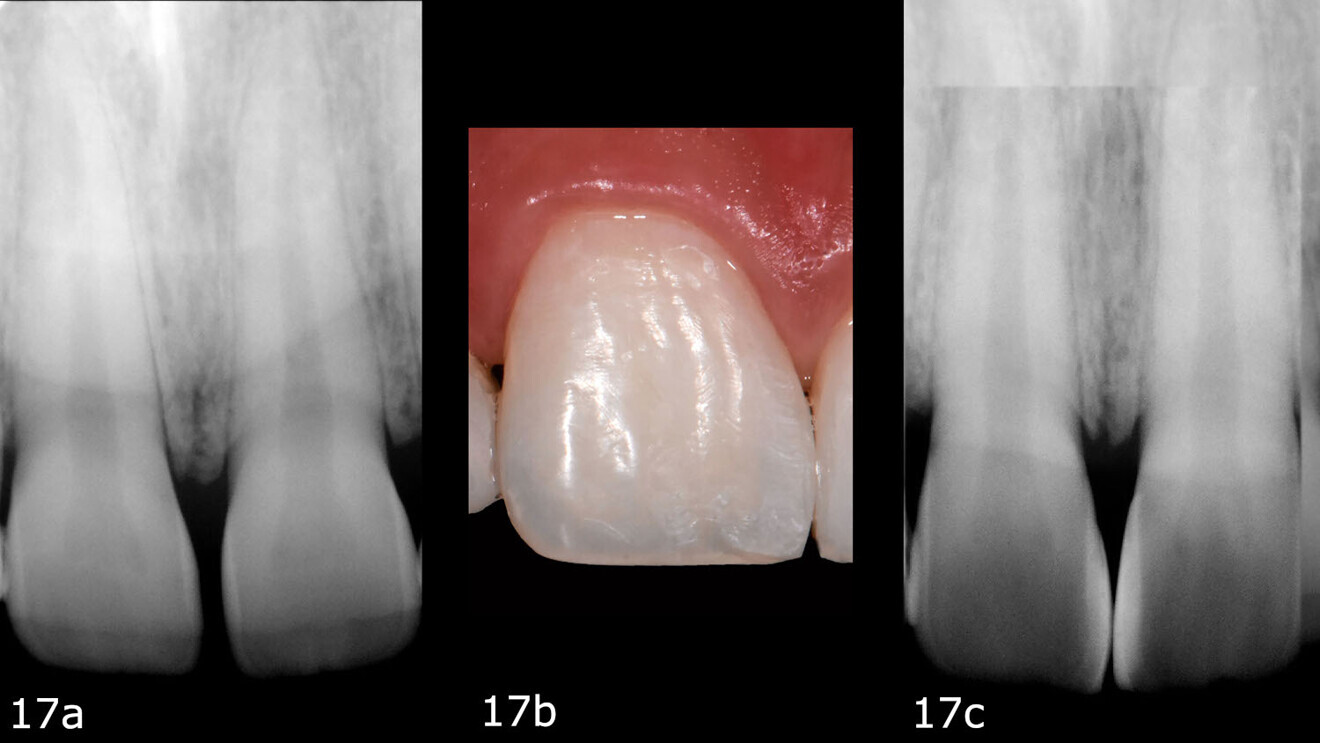

Once the dental dam had been removed, abrasive discs were used (Sof-Lex, 3M) to optimise the mesial margins by reducing hinderances to the passage of dental floss.15 The shine and three-dimensionality of the treated surface were enhanced by polishing with a rubber cup and a diamond paste or zirconium powder16 (Fig. 16), all the while paying attention to the interdental spaces.17 To complete the polishing, a felt disc (Super-Snap Buff Disk, SHOFU) and a diamond-impregnated polishing paste (DirectDia Paste, SHOFU) were applied to the enamel, and the final polishing step was performed using silicone polishers (Dimanto, VOCO). Conventional radiographic checks were conducted to confirm that the restoration had been optimally carried out and was free of potential infiltration sites (Fig. 17). Radiographs would serve as confirmation at the DSD check.

At the six-month follow-up appointment, the patient’s situation was very different to that at the initial consultation. There was proper closure of the interdental gaps and consequent formation of papillary tissue that harmonised the shape of the attached gingiva and of the reconstructed enamel perimeter (Figs. 18–21). In addition, the examination showed no fractures of the restoration or wear, no marginal discoloration or other staining, adequate marginal seal, adequate colour stability and translucency, very good surface structure and anatomical shape, excellent contact points, very good integrity of the teeth and no inflammation.

Fig. 21a: Six-month follow-up.

Fig. 21b: Six-month follow-up.

Fig. 21c: Six-month follow-up.